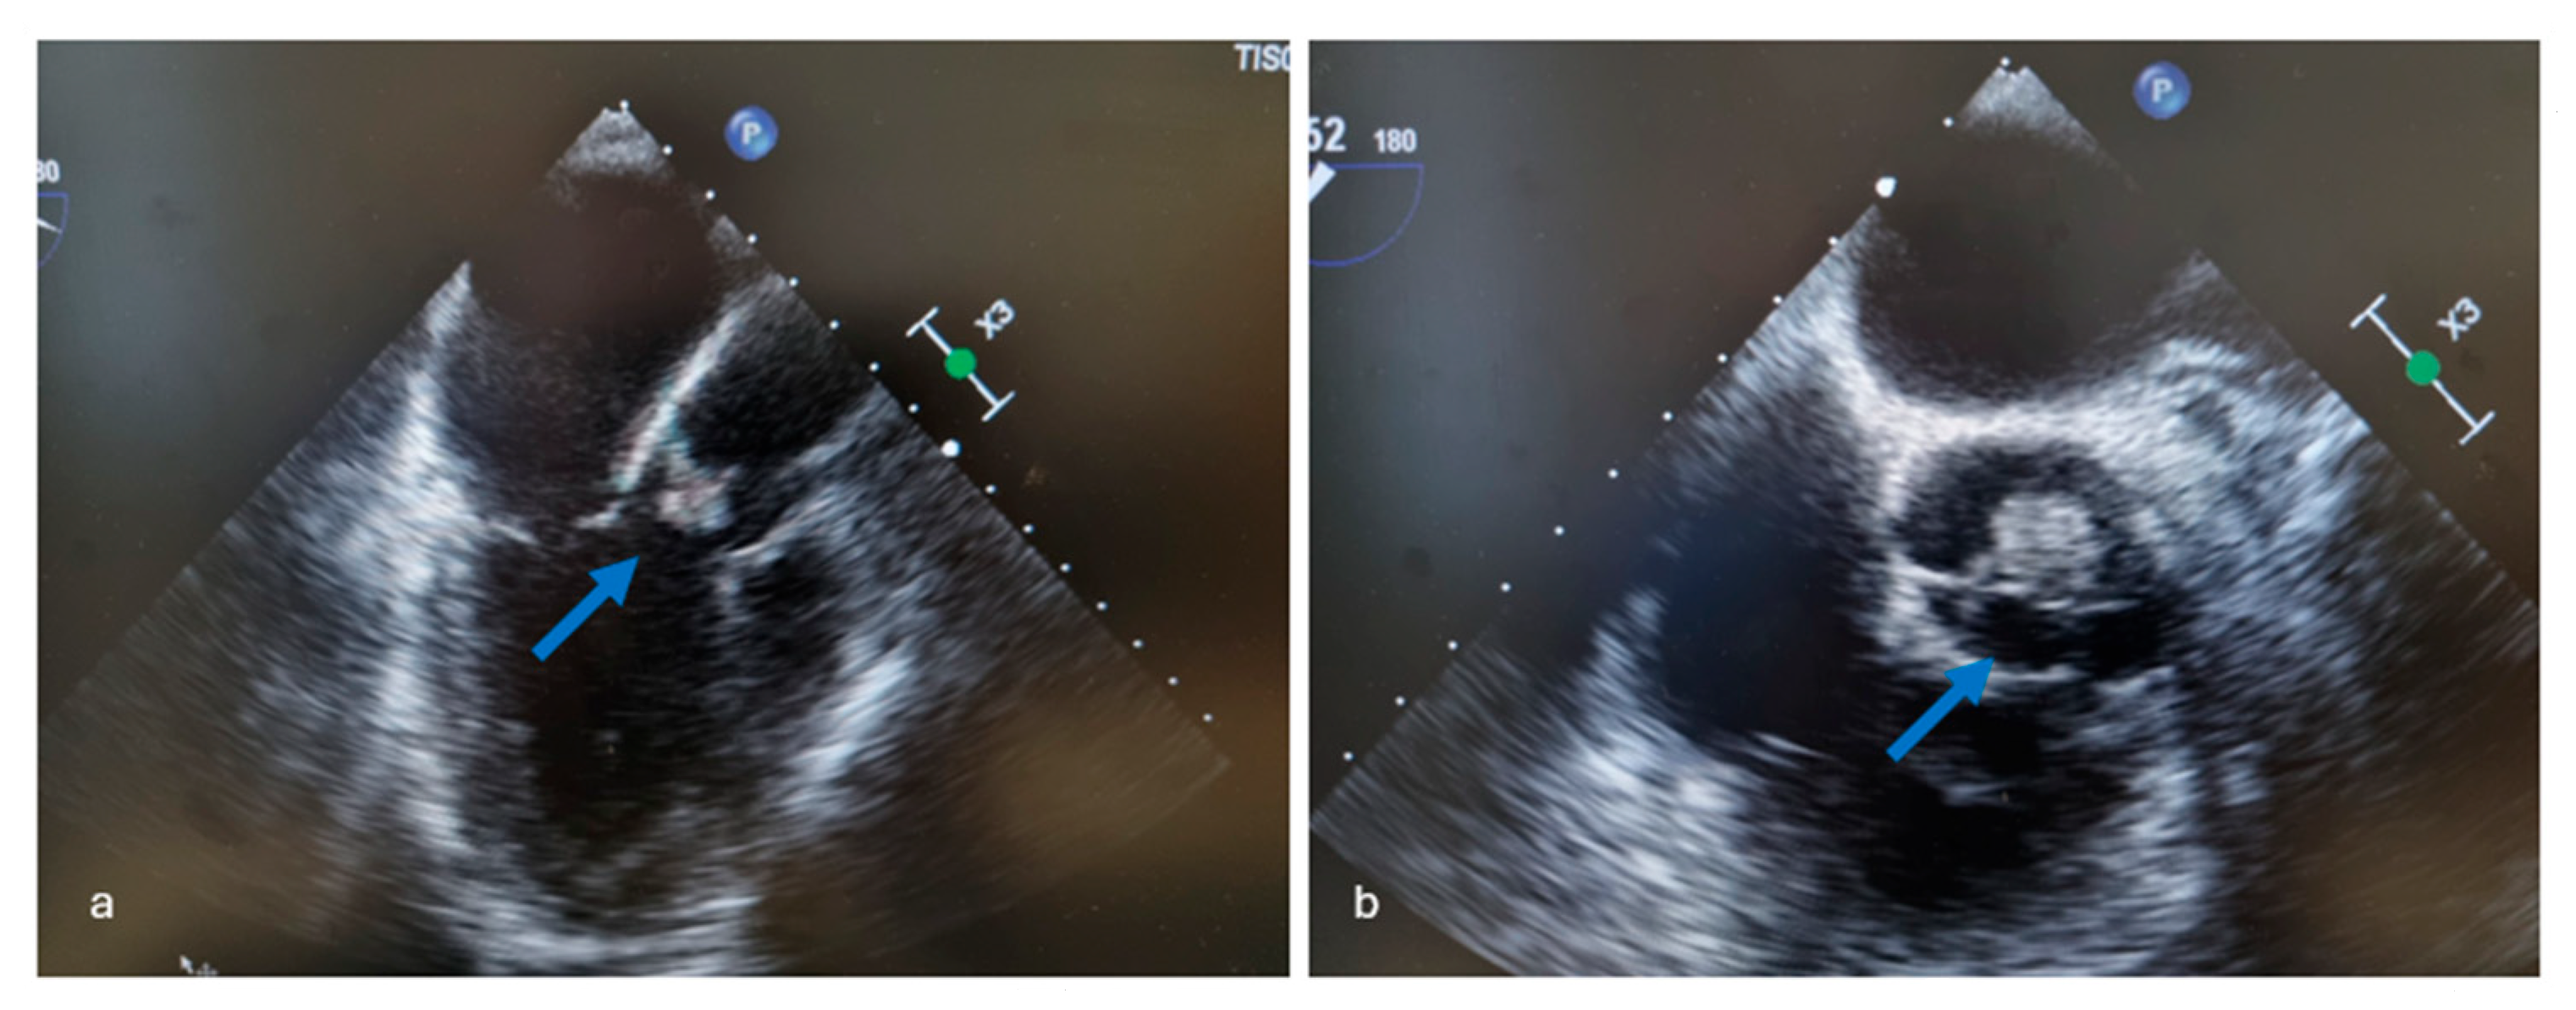

4.2. Imaging